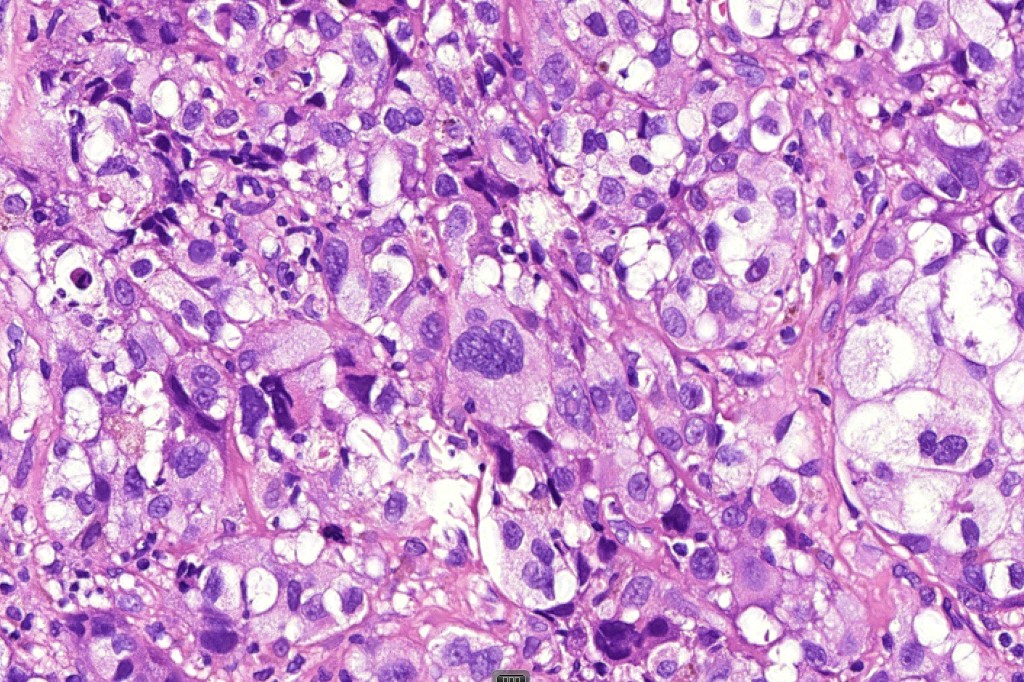

These are very rare variants of amelanotic or virtually amelanotic melanoma where a primary melanoma or a metastasis shows partial (DN) or complete loss (UN) of recognizable histological and immunohistochemical features. The histology may lead the pathologists to consider lymphoma, sarcoma, anaplastic carcinoma or a small cell tumor. Some examples of rhabdoid melanoma & melanoma with heterologous differentiation probably belong in this category. Ultimately, if there is no identifiable/recognizable primary tumor, diagnosis may only be comfortably made with next-generation sequencing. In the cases presented below, immunohistochemistry was of value in determining the melanoctic nature of the tumor (undifferentiated melanoma).